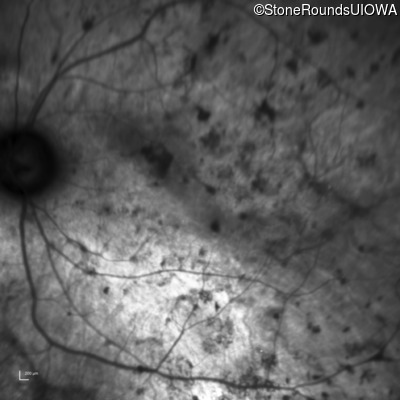

Age at visit: 25 years